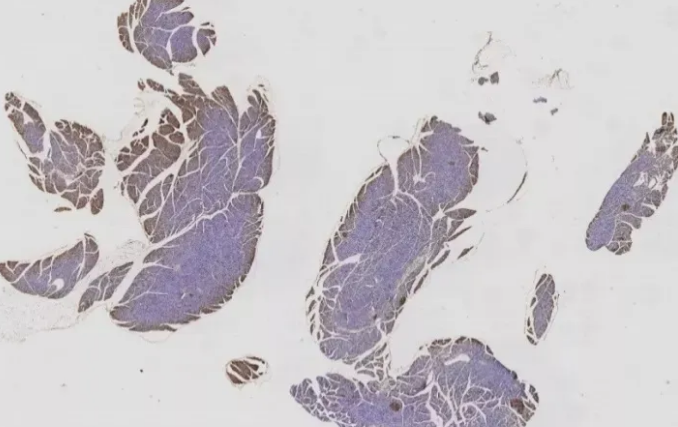

二、內(nèi)源性過氧化物酶

彌散性非特異性背景,可能是由內(nèi)源性過氧化物酶引起的(如圖2)。因此,封閉液要現(xiàn)配現(xiàn)用,充分封閉,一般15min。